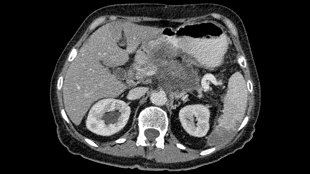

胰腺癌,圖片來自維基共享資源|Hekkerhoff

來自英國劍橋大學(xué)腫瘤研究所(Cancer Research UK Cambridge Research Institute)的David Tuveson和他的同事們注意到胰腺癌(pancreatic cancer)細胞似乎特別能夠抵抗脅迫應(yīng)激,并且追蹤這種強有力的抵抗性后發(fā)現(xiàn)是因為胰腺癌細胞相對于正常的細胞而言含有較低水平的ROS。